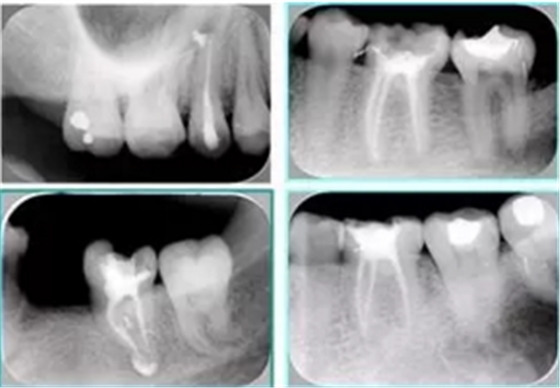

2. X 線片

共有 4 張 X 線片,分別是術(shù)前、診斷絲 、主牙膠尖確認(rèn)、術(shù)后。

( 1 )術(shù)前:術(shù)前 X 線片用來了解牙齒的大概情況。術(shù)前預(yù)期為多根牙時 X 線片應(yīng)偏頭拍攝。

( 2 )診斷絲:根據(jù)術(shù)前 X 線片進(jìn)行開髓、根管的初步預(yù)備后,需要插入診斷絲,用來指示工作器械位置。常用 10 號或 15 號擴大器作為診斷絲插入牙髓腔。

( 3 )主牙膠尖確認(rèn):通過術(shù)前預(yù)期和診斷絲診斷,明確工作長度、牙根走向,進(jìn)行根管預(yù)備。之后應(yīng)進(jìn)行主牙膠尖(中銼)確認(rèn),已明確根管是否適合充填。

( 4 )術(shù)后:觀察治療效果。